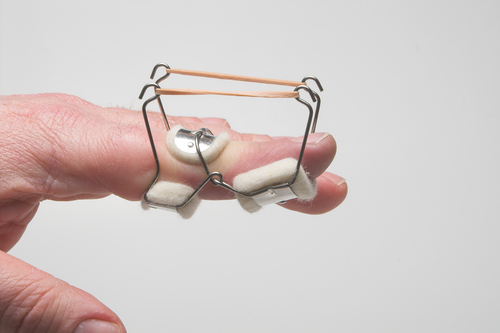

Rapid Review: Is Finger Splinting Necessary after Flexor Tendon Repair?

Outcome of Flexor Tendon Repair Using Eight-Strand Core Stitch Without Postoperative Finger Splinting Reference: El-Gammal, T. A., Kotb, M. M., Ragheb, Y. F., El-Gammal, Y. ...

儿童扳机指的手术与保守治疗

Jia, L.、King, JD、Goubeaux, C.、Belardo, ZE、Little, KJ、Samora, JB、Marks, J.、&Shah, AS (2023)。演示和管理...

影响手部急性创伤性肌腱损伤患者矫形器依从性的因素

萨瓦什 (Savaş) 和艾多安 (Aydoğan) Ç. (2020)。急性创伤性手肌腱修复后影响矫形器依从性的因素:一项前瞻性队列研究。手部治疗杂志,S0894113020301848。 ...